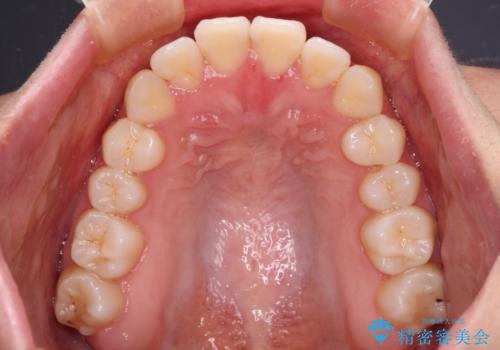

- 前歯のクロスバイトが気になり、インビザラインによる矯正治療を希望して来院された患者様です。

上顎側切歯(上の真ん中から2番目の歯)が舌側転位している場合、インビザラインでは仕上げきれないことが多く、更には無理して動かそうとすると歯髄壊死を起こすリスクが高いと言われています。

インビザラインで歯列を移動する前に、上顎前歯をワイヤー矯正で整え、その後上下歯列をインビザラインにて矯正治療を行うこととしました。

舌側転位している側切歯特有の、切縁の位置が不揃いであったり、根元が内側に引っ込んだ状態であったりという、インビザライン独特の仕上がりになることなく、きれいに整った歯列とすることができました。